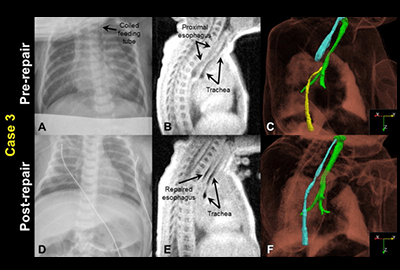

Neonatal MRI

The goal of this research is to translate new and innovative MRI techniques to sick and challenging patient populations, like those that are born prematurely. Our studies include both proton MRI and hyperpolarized gas MRI in infants. This has begun to revolutionize our understanding of both parenchymal and airway components of disease. This research is being conducted in partial collaboration with the BPD Center.